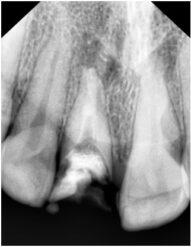

Realizamos radiografía panorámica y periapical de la zona, donde podemos observar que le queda un resto radicular, el cual presenta una gran infección periapical, parece llevar intraconducto un material intraconducto y una obturación provisional sobre el mismo. Esta obturación provisional está completamente suelta y filtrada.

- Apicoformación con MTA del resto radicular que presenta para la formación de un stop apical y su posterior tratamiento endodóntico con técnica de obturación termoplástica.

Procedemos a la realización del tratamiento conservador. Empezando por la apicoformación, endodoncia y restauración del diente. A continuación podemos ver una sucesión de radiografías con la evolución del tratamiento del paciente y la intervención realizada.